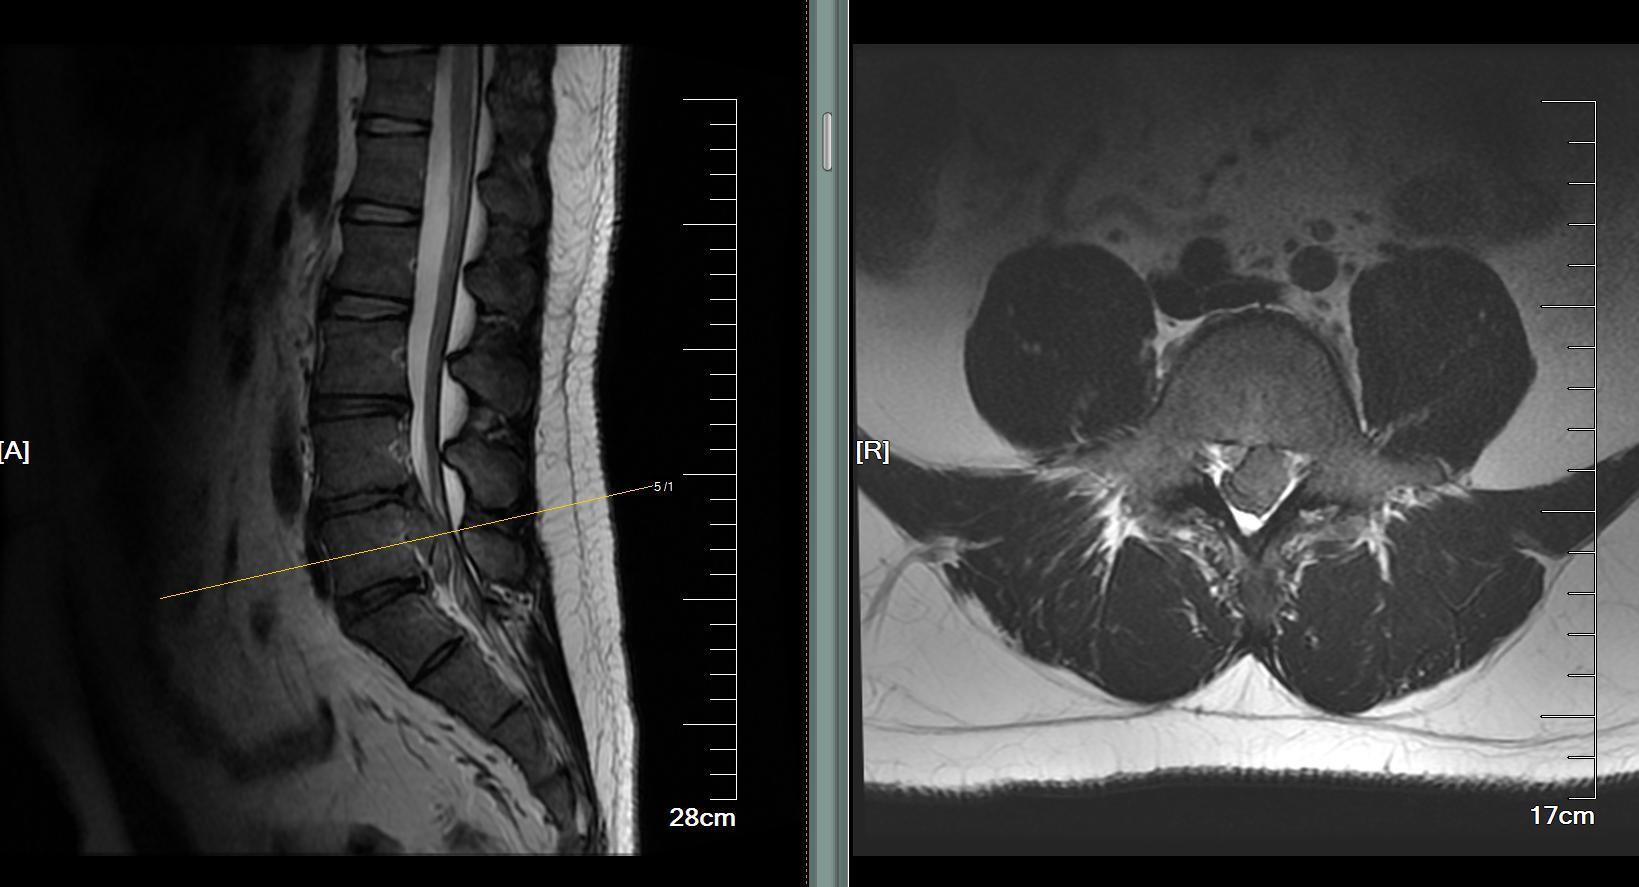

【疾病类型】腰椎间盘突出症,腰4-5,尾侧超高度游离

首先给老张进行了仔细查体,腰部有压痛、叩击痛,并向左下肢放射,左下肢直腿抬高试验40°,加强试验阳性,左足拇指背伸肌力3级,肛周皮肤感觉麻木。跟老张及其家人交代病情,第一,腰痛伴有下肢放射性疼痛,考虑存在腰椎间盘突出;第二,出现阳性体征,有肌力减弱、感觉减退等神经损害的体征,提示有腰椎间盘突出并压迫了神经;第三,虽然大小便暂时没有异常改变,但肛门周围有异常感觉,提示马尾神经受损;综合相关情况,考虑老张目前有腰椎间盘突出,并且可能突出比较严重。急诊查了腰椎核磁,果然,腰4-5水平间盘突出,并且向尾侧游离到腰5-骶1间隙水平,属于超高度游离,神经根及马尾神经严重受到挤压。